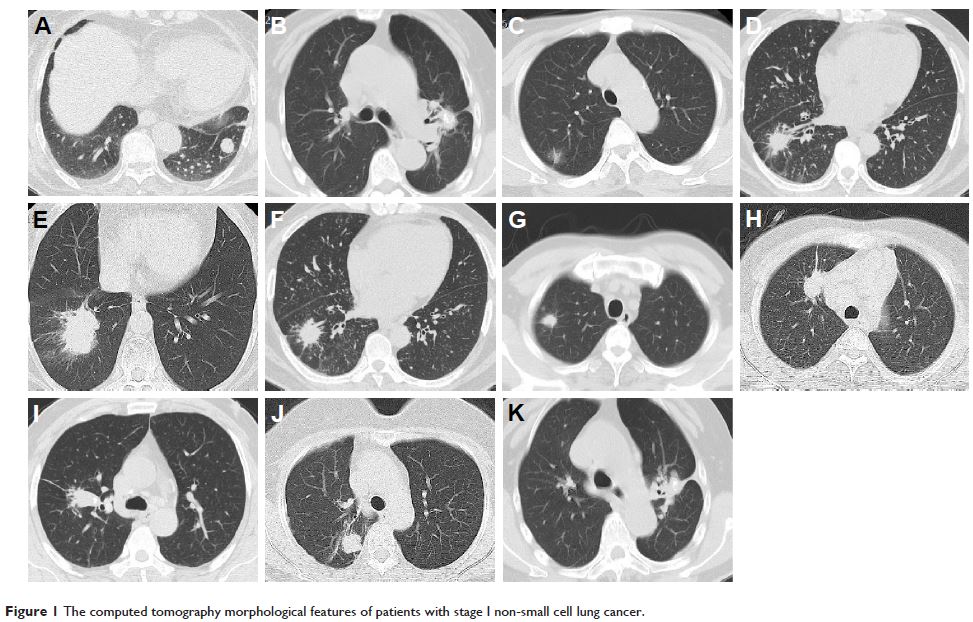

- 作者:Jun Ma, Yun-Long Yang, Ye Wang, Xue-Wei Zhang, Xue-Song Gu, Zhen-Chang Wang

- 期刊:OncoTargets and Therapy